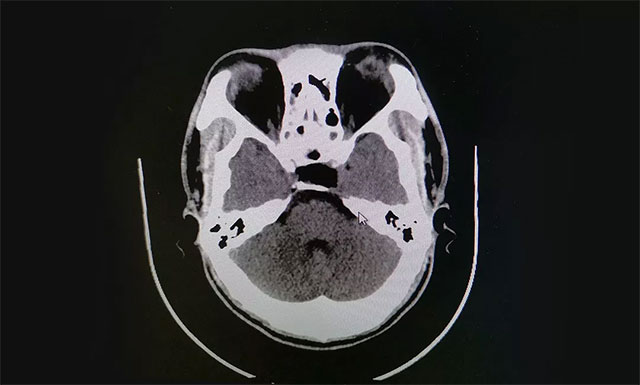

术后根据病理分析,该肿瘤为GH腺瘤。术后患者视物重影已消失,视力明显改善,目前正在康复中。

▲ 术后影像显示肿瘤被切除